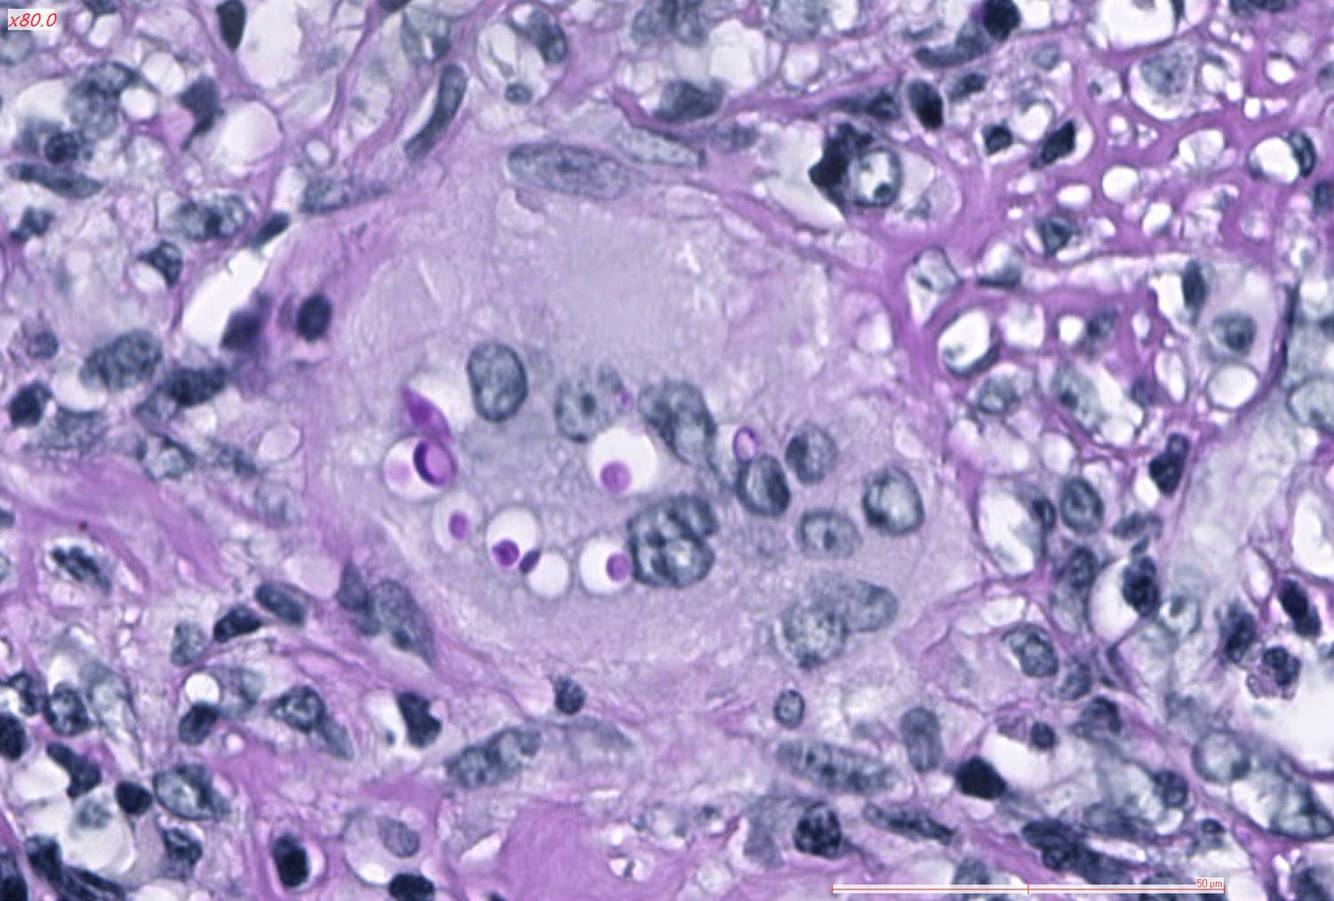

How is the Diagnosis of Cutaneous Cryptococcus infection typically Confirmed?

Lesion Biopsy with Histopathological examination